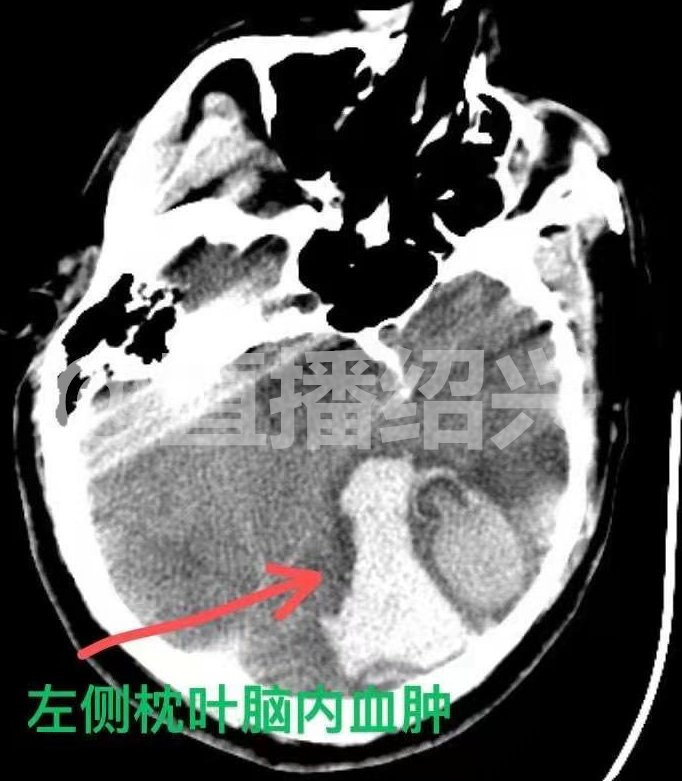

(箭头所指为出血处)

原来,老吴的工友到中午干完活,发现老吴还趴在桌上睡觉,才意识到情况不对了,工友们连声呼喊老吴,但老吴已经不省人事了,于是大伙连忙拨打了120急救电话把老吴送到了医院。老吴的主治医师董昌明告诉采访人员,老吴刚被送到医院的时候,瞳孔已经放大了,随时可能有生命危险,医院立即对老吴进行了手术。

在手术过程中医生发现老吴脑内有大量的畸形血管,其中一条血管甚至长得跟灯泡一样。